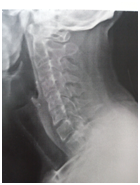

The baseline score (before starting our treatment) on BASDAI was ‘4.5’ and after 6 months completion of treatment the score on BASDAI was reduced to ‘0.9’ i.e., there was ‘80%’ of improvement found. Good improvement was found in ‘fatigue/tiredness’ (80% relief), ‘neck/back/hip pain’ (75% relief), ‘tenderness’ (80% relief), and ‘intensity as well as duration of morning stiffness’ (88% relief). Patient’s sleep, appetite and quality of life were improved. There was noticeable improvement observed (thorasic kyphosis/stooping of neck forward) in X– Ray of cervical spine (Figures 3&4). Knee joint pains were totally relieved and patient’s posture got improved along with relief in low back ache and neck pain. No adverse effects were reported by the patient. The patient got clinically meaningful improvement by internal medicines along with dietary restrictions (advised to avoid dairy products and to drink hot water) and life style changes. Ayurvedic treatment seems to be promising in the management of AS with in short period of time and without causing any adverse effects.

Figure 3 X – Ray of Cervical spine – Lateral view (dated on 08.08.2016).

Figure 4 X – Ray of Cervical spine – Lateral view (dated on 20.12.2016).